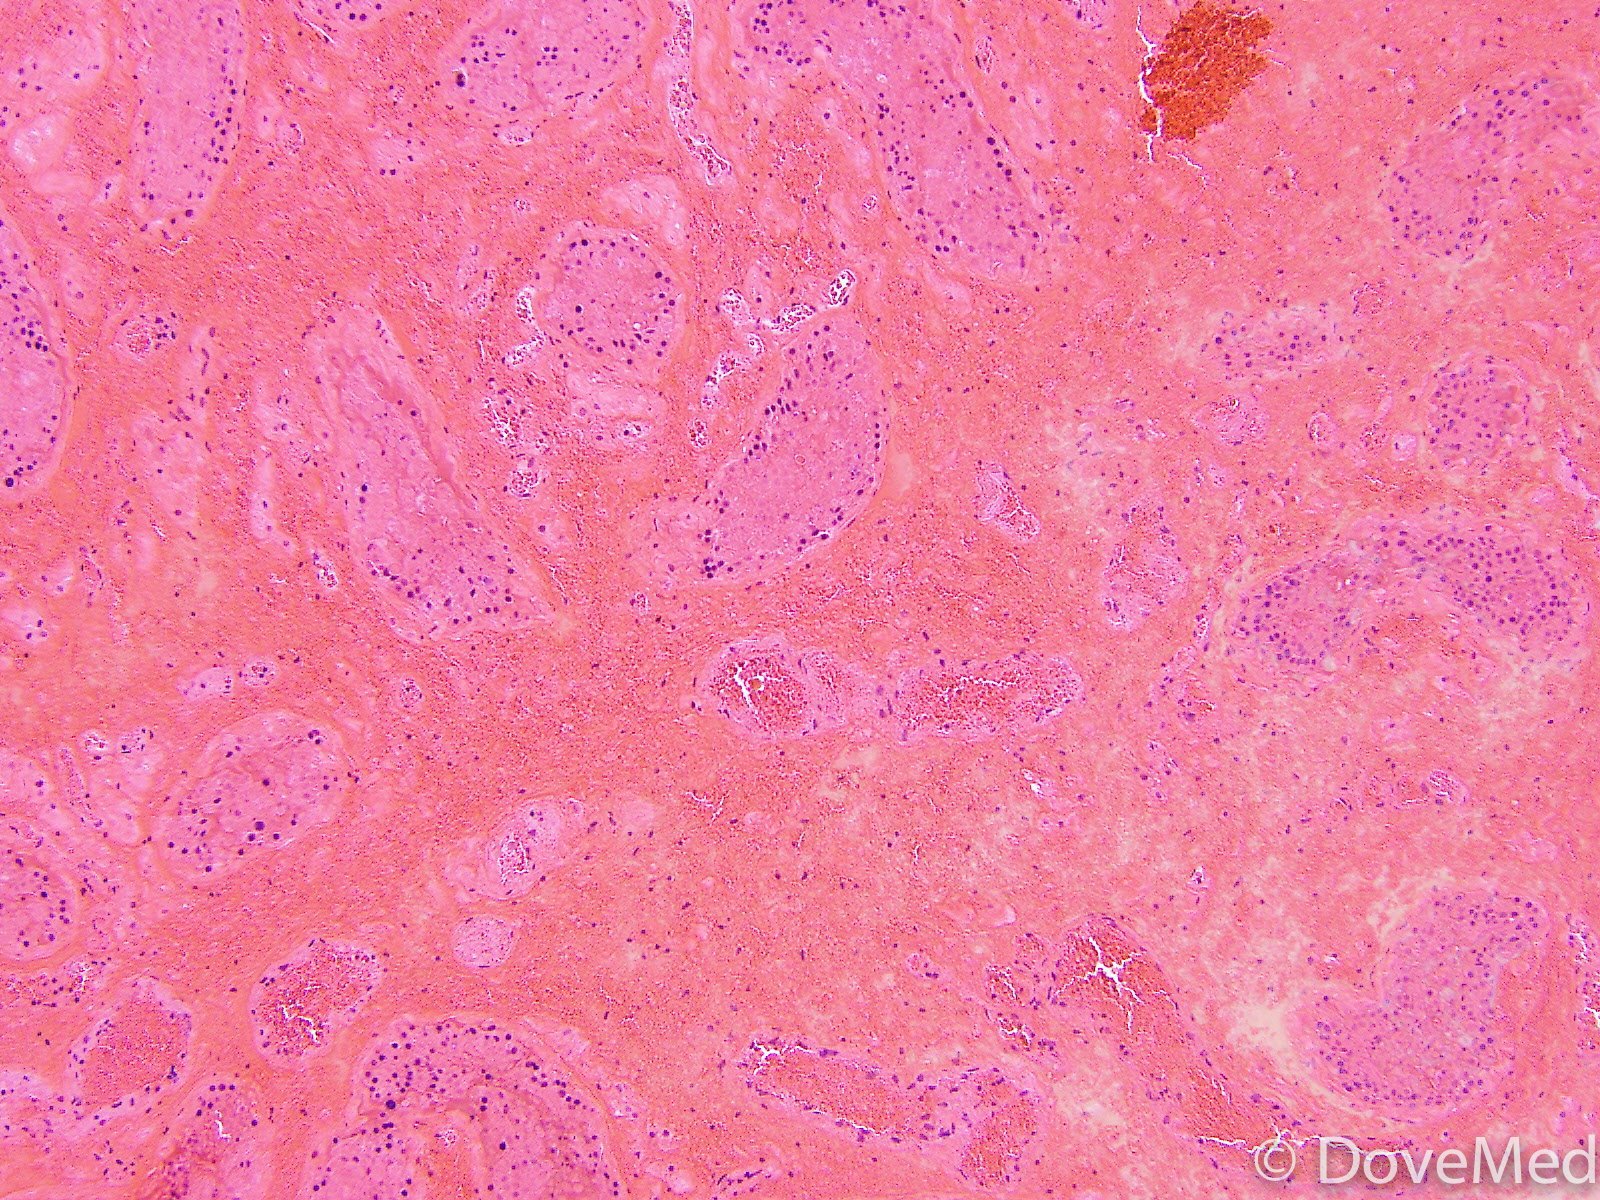

from www.dovemed.com